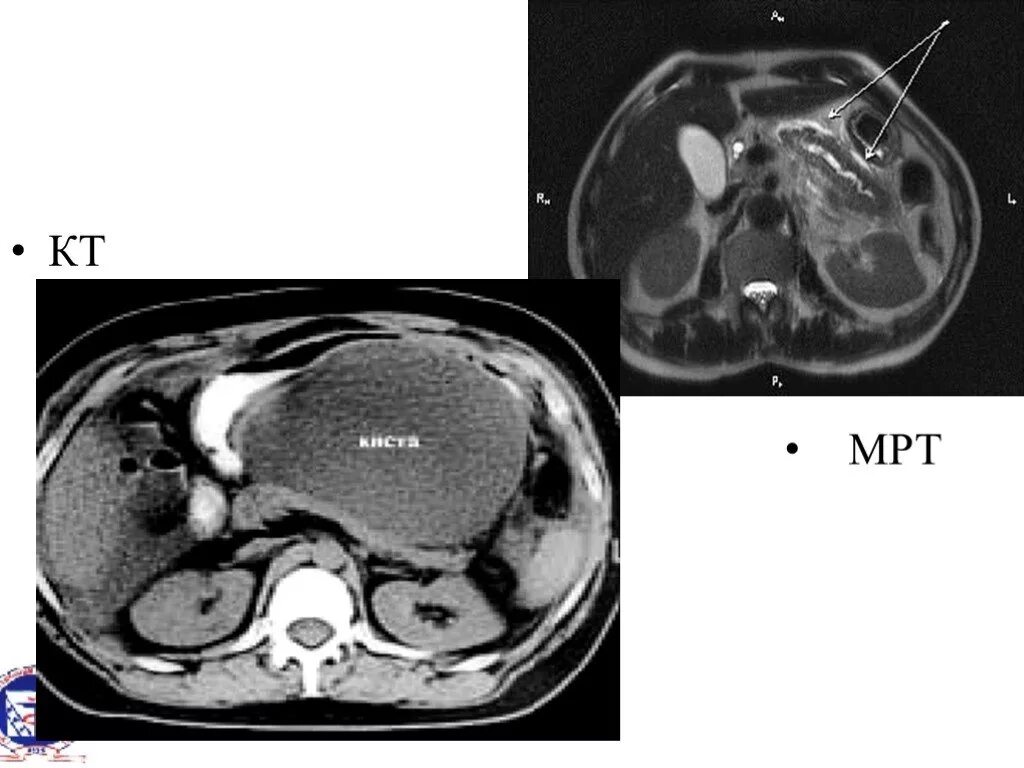

Можно заменить кт на мрт